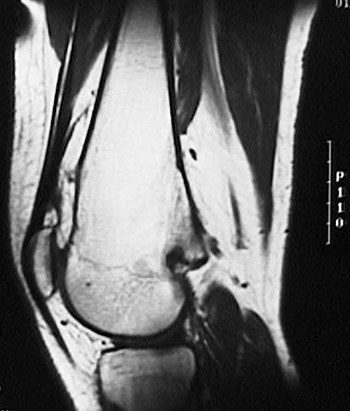

The sagittal MRI scan above demonstrates an osteochondroma projecting laterally from the metaphyseal region of the distal femur.